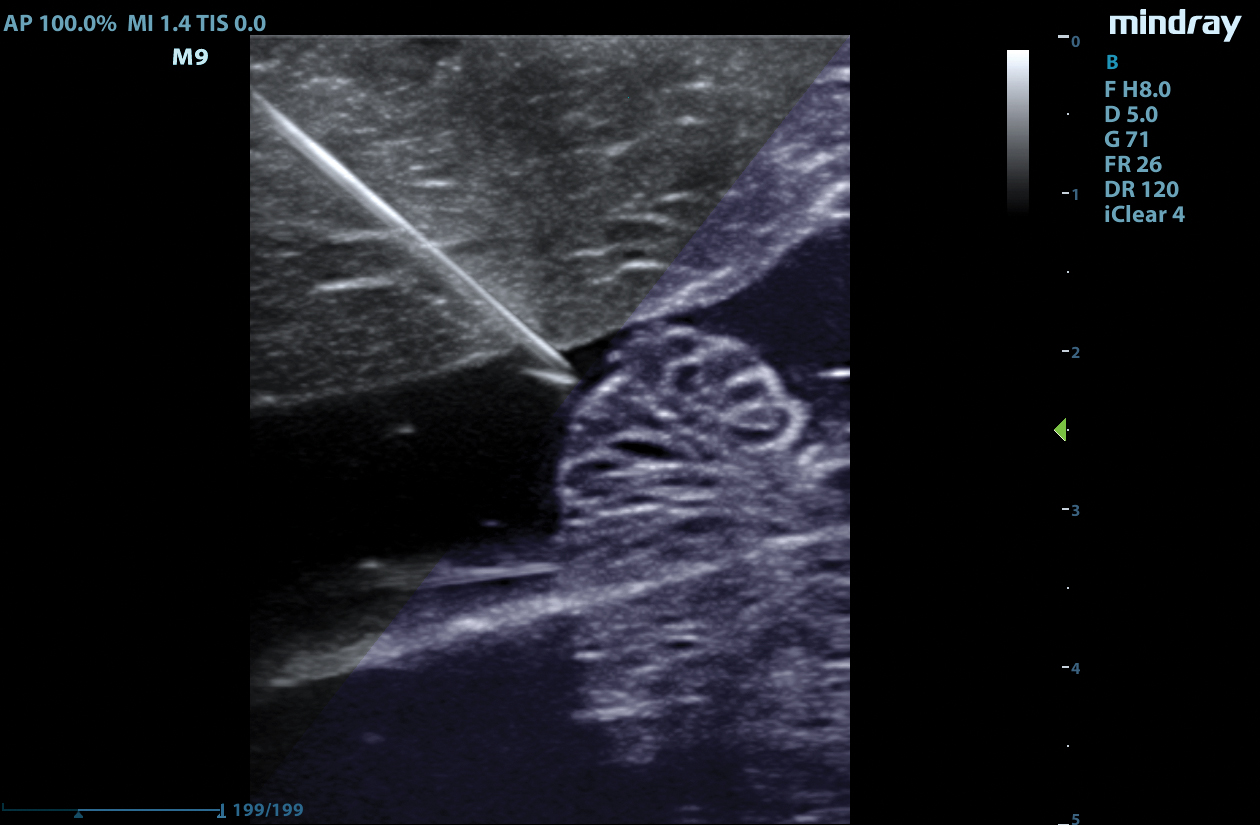

Equipped with single crystal transducers and 3T™ technology for a wide range of exams, the M9 System is a versatile platform for advanced imaging in the vascular lab, emergency departments, critical care environments, and anesthesia practices. The System’s slim profile and ergonomic design allow for effortless flexibility and mobility. Whether it be ultrasound guided procedures at the patient’s bedside or transesophageal echocardiography (TEE) imaging in the critical care unit, this platform can do it all.